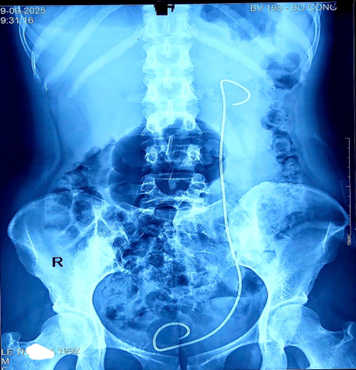

Ảnh 2: Quá trình phẫu thuật

Ê-kíp phẫu thuật đã tiến hành:

-Nội soi niệu quản tán sỏi bằng Laser.

-Rút Sonde JJ cũ tồn tại 15 năm và thay Sonde JJ mới.

-Nội soi tán sỏi qua da thận trái để xử lý toàn bộ sỏi thận.

Nhờ sự chuyên nghiệp, cẩn trọng và giàu kinh nghiệm, ca phẫu thuật diễn ra thành công tốt đẹp. Bệnh nhân sạch sỏi, ổn định sau mổ và được xuất viện chỉ sau 3 ngày.

Ảnh 3: Hình ảnh sạch sỏi sau mổ